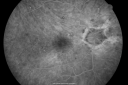

Diabetic Macular Edema with Circinate Exudate

74-year-old man has diabetic macular edema in both eyes and background diabetic retinopathy.  His vision has blurred over the last few months.  His blood sugars have been fluctuating.

VISUAL ACUITY: Vision OD is 20/25, OS is 20/80